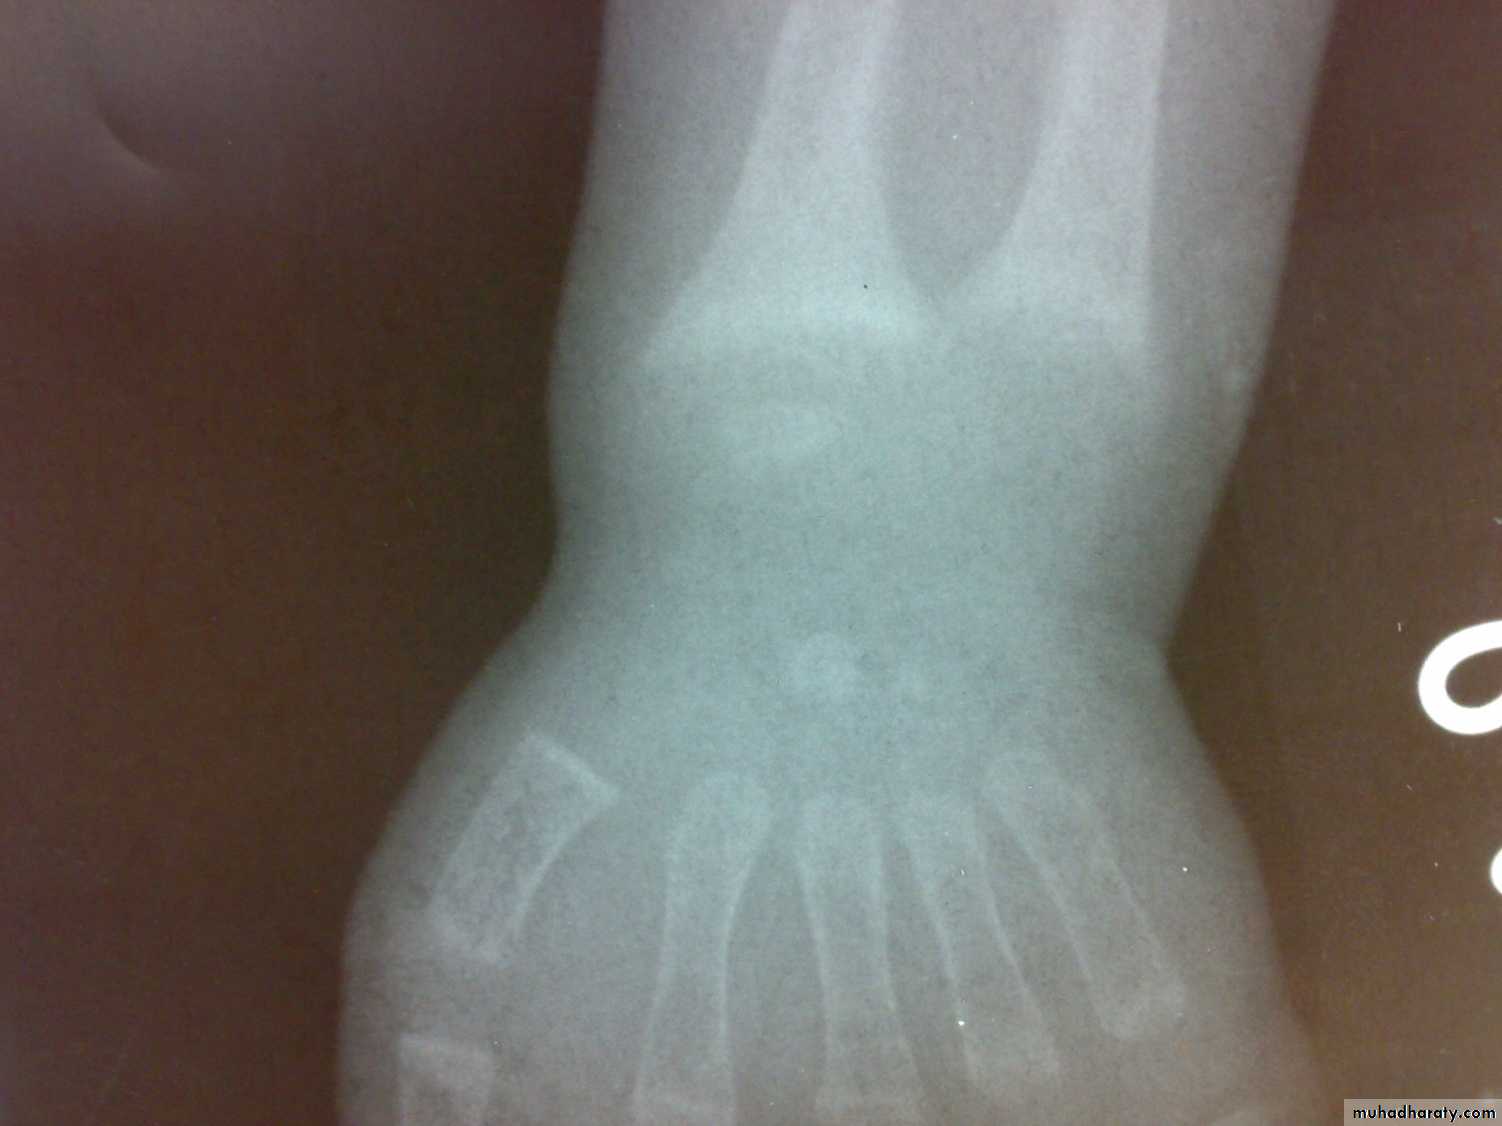

Osteomalacia and ricketsinadequate mineralization of bone

Bone tissue throughout the skeleton is abnormally calcified and therefore soften ( Osteomalacia).Rickets and Osteomalacia is same disease.

Losser’s zone

decreased serum phosphate

elevated serum alka. Phosphatase.

Ca × p< 2.4 mmol/ L